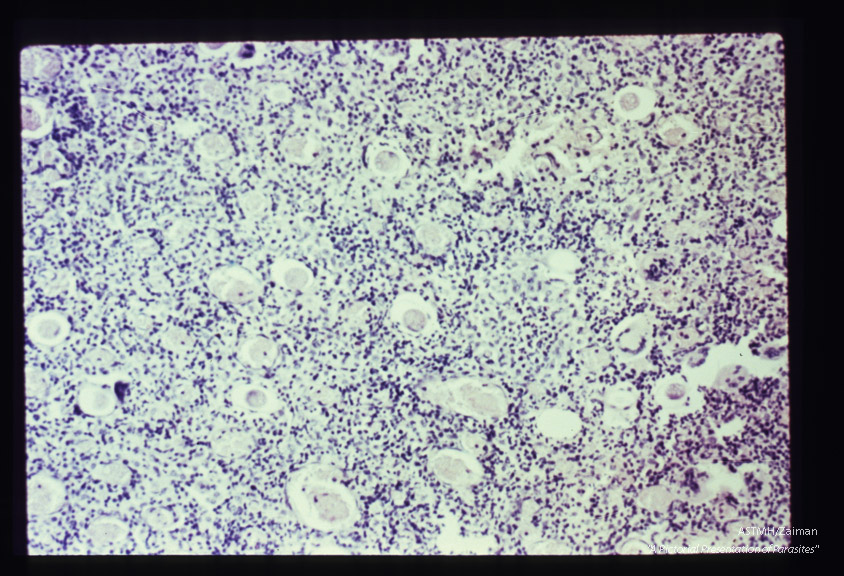

Eggs in peritoneum. The egg shell, without the mamillated coat, can be seen.

Description: Eggs in peritoneum. The egg shell, without the mamillated coat, can be seen.